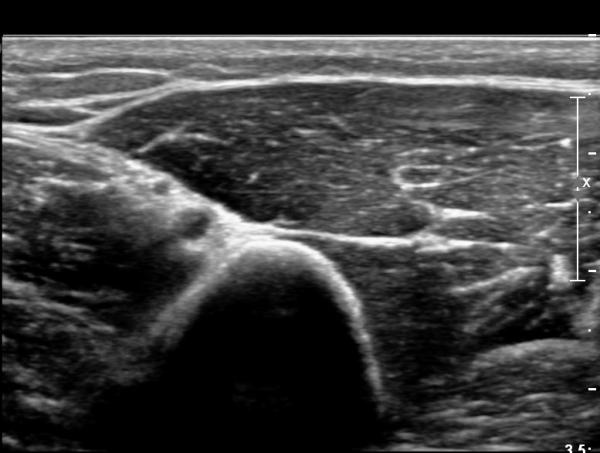

¿ä°ñ °í¶û¿¡¼­ ¿ä°ñ½Å°æ Ⱦ´Ü¸é°Ë»ç»ó ¿ä°ñ½Å°æÀÇ °æ¹ÌÇÑ Àú¿¡ÄÚ ºÎÁ¾ÀÌ °üÂûµÈ´Ù(»çÁø 2).

ŽÃËÀÚ¸¦ Á¶±Ý ¸»´ÜÀ¸·Î À̵¿ÇÏ´Ï ¿ä°ñ½Å°æ Àú¿¡ÄÚ ºÎÁ¾ÀÌ ´õ¿í ¶Ñ·ÈÇѵ¥(»çÁø 2),